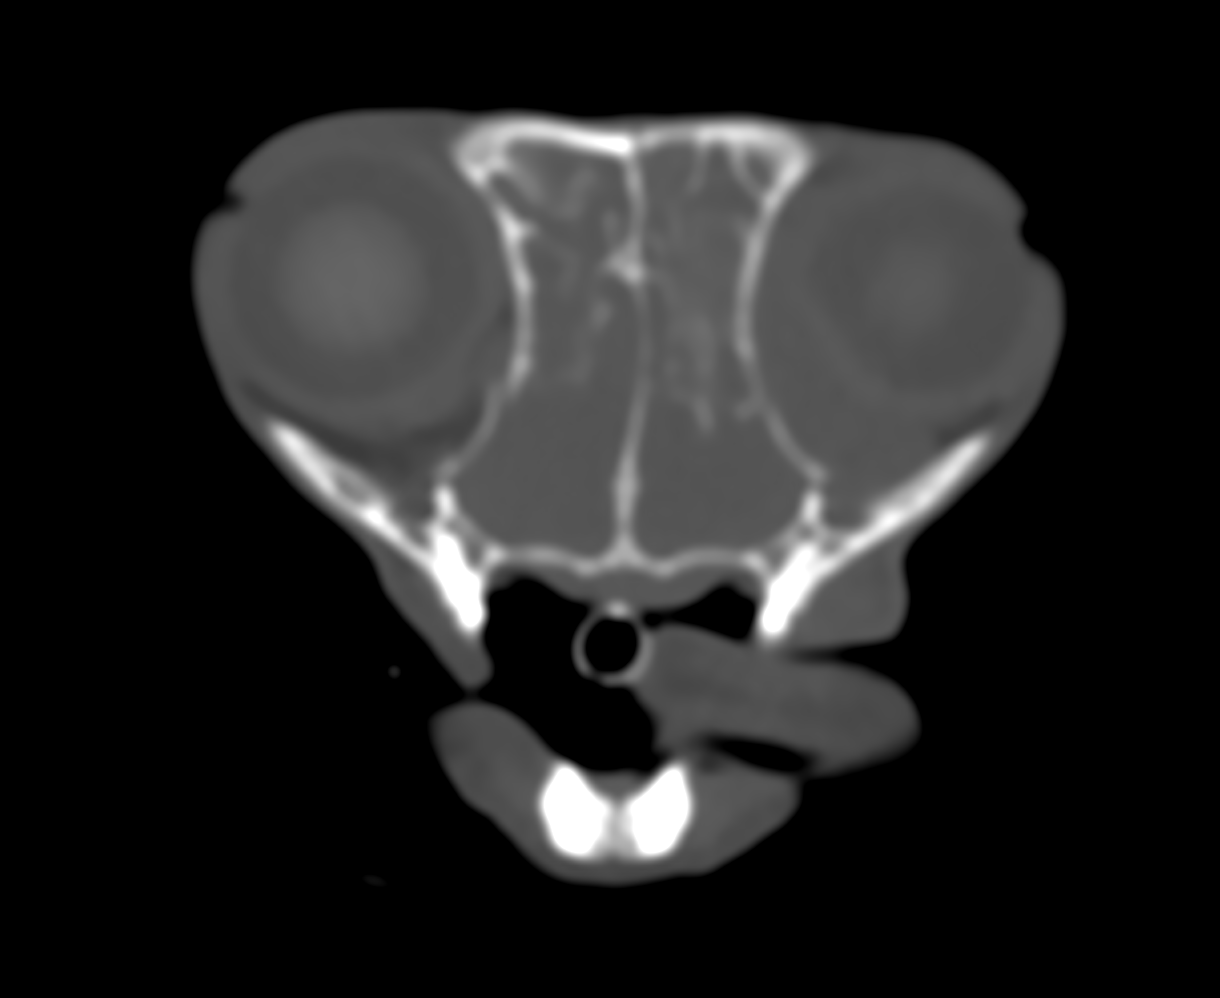

中でも鼻腔内のリンパ腫については、鼻の中であるため外からは見えず、骨に囲まれているため発見や診断が難しいタイプとなります。発生率もリンパ腫の中ではそれほど多いタイプではありません。

CTの映像で見えた通り、発見時にはかなり進行して呼吸も苦しく、目も飛び出してしまっておりました。